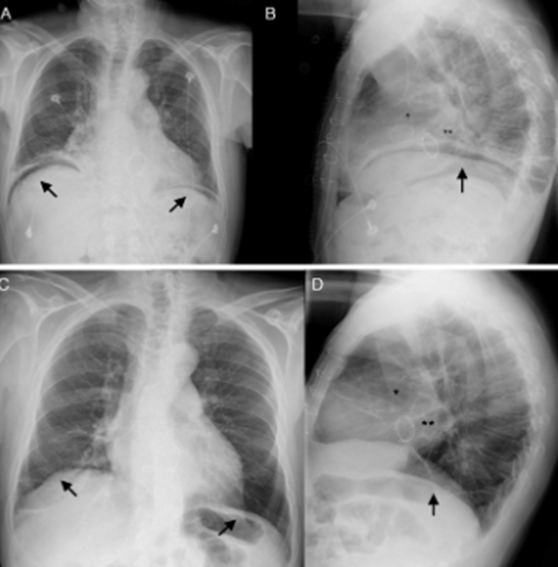

Aun que presentamos radiografia de Torax para ilustrar la patología, es normalmente con abdomen en bipedestación como se localiza este hallazgo.

A. Radiografía anteroposterior de tórax mostrando la presencia de neumoperitoneo a ambos lados diafragmáticos (flechas). B.Radiografía lateral de tórax mostrando el neumoperitoneo (flecha). C-D: Radiografía anteroposterior y lateral respectivamente, realizadas al mes tras la intervención, en las que se comprueba la resolución del neumoperitoneo (flechas), con una mínima elevación del hemidiafragma derecho (flecha), en ausencia de derrames pleurales a nivel bilateral. Los alambres esternales son patentes así como la visualización de las prótesis valvular aórtica mecánica y mitral biológica.